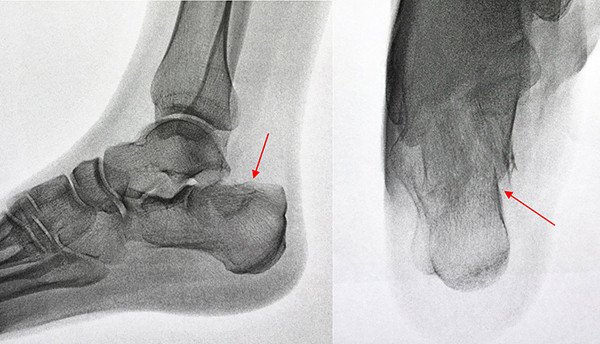

Vorstellung einer 32jährigen Patientin in unserer Sprechstunde, welche sich im Vorjahr nach einem Sturz von einer hohen Mauer eine Fraktur des Fersenbeines zugezogen hatte (Abb. 1 und 2). Auswärtig wurde diese durch eine Plattenosteosynthese versorgt (Abb. 3), der postoperative Verlauf gestaltete sich soweit komplikationslos.